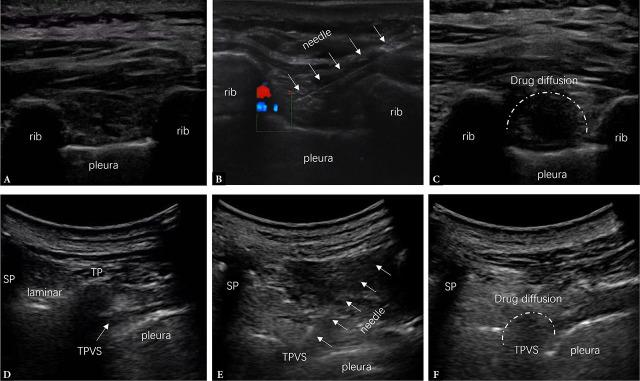

To assess whether ultrasound (US)-guided intercostal nerve blocks (ICNBs) provide non-inferior efficacy in the management of acute zoster pain (ZAP) and potential prophylaxis for post-herpetic neuralgia as compared to conventional thoracic paravertebral blocks (TPVBs).

A total of 192 patients with ZAP were reviewed. Their records were stratified into two cohorts: those who underwent US-guided TPVBs (TPVB cohort) and those who received US-guided ICNBs (ICNB cohort). The ICNB cohort was matched using a propensity score method in a 1:1 ratio. The primary endpoint was non-inferiority of (HZ)-related illness burden within 30 days (HZ-BOI) post-procedure. Secondary outcomes included procedure time, rescue analgesic use, post-herpetic neuralgia occurrence, health-related quality of life, and adverse events.

Mean score of HZ-BOI was 87.92 ± 21.84 and 85.64 ± 17.01 in the TPVB and ICNB cohorts, respectively, with a mean difference of 2.28 (95% confidence interval (CI): -5.68, 10.24). Non-inferiority was met, as the 95% CI for the absolute difference in HZ-BOI fell within the predefined non-inferiority margin of 15 points. Comparable improvements in post-herpetic neuralgia incidence, EQ-5D-3L scores, and rescue analgesic requirements were observed in both cohorts across all follow-up time points (all >0.05). In contrast, the ICNB approach was associated with shorter procedure times ( <0.001) and reduced discomfort and pain during needle insertion ( <0.001). There were no complications, including pneumothorax, nerve injury, or intravascular injection in either study cohort.

US-guided ICNBs were non-inferior to TPVBs in alleviating ZAP and preventing post-herpetic neuralgia, while also demonstrating a favorable safety profile. These findings suggest that the ICNB technique might be a promising alternative for managing ZAP.